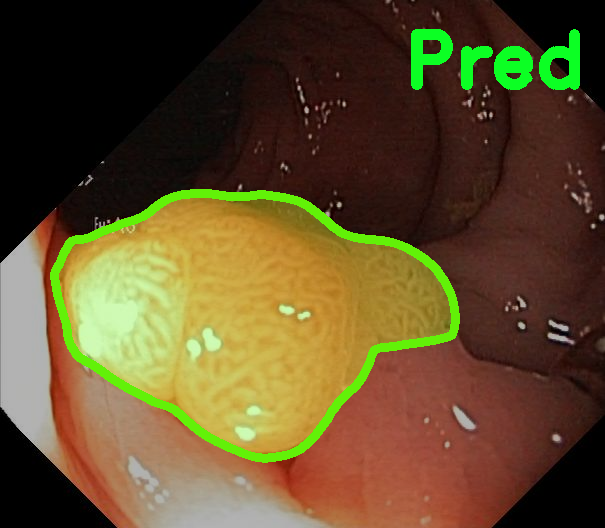

TransFuse is evaluated on both 2D and 3D datasets to demonstrate the effectiveness. As different medical image segmentation tasks serve different diagnosis or operative purposes, we follow the commonly used evaluation metrics for each of the segmentation tasks to quantitatively analyze the results. Selected visualization results of TransFuse-S are shown in Fig. 2.

Results of Polyp Segmentation. We first evaluate the performance of our proposed method on polyp segmentation against a variety of SOTA methods, in terms of mean Dice (mDice) and mean Intersection-Over-Union (mIoU). As in Tab. 3, our TransFuse-S/L outperform CNN-based SOTA methods by a large margin. Specifically, TransFuse-S achieves 5.2% average mDice improvement on the unseen datasets (ColonDB, EndoSene and ETIS). Comparing to other transformer-based methods, TransFuse-L* also shows superior learning ability on Kvasir and ClinicDB, observing an increase of 1.3% in mIoU compared to TransUnet. Besides, the efficiency in terms of the number of parameters as well as inference speed is evaluated on an RTX2080Ti with Xeon(R) Gold 5218 CPU. Comparing to prior CNN-based arts, TransFuse-S achieves the best performance while using only 26.3M parameters, about 20% reduction with respect to HarDNet-MSEG (33.3M) and PraNet (32.5M). Moreover, TransFuse-S is able to run at 98.7 FPS, much faster than HarDNet-MSEG (85.3 FPS) and PraNet (63.4 FPS), thanks to our proposed parallel-in-branch design. Similarly, TransFuse-L* not only achieves the best results compared to other Transformer-based methods, but also runs at 45.3 FPS, about 12% faster than TransUnet.